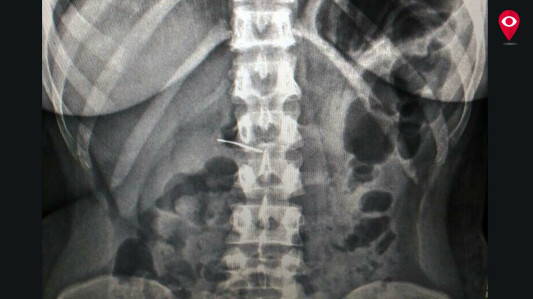

The doctors conducted an endoscopy and found that the needle was stuck in her small intestine. She was immediately admitted to the hospital right after 6 hours of swallowing the needle. Here, with the help of ‘Single Balloon Enteroscopy’ doctors took out the needle without any surgery.

“As the needle was stuck in the small intestine (Jejunum), there was no way needle would have come out naturally through poop. So we thought of using the technique namely ‘Single Balloon Enteroscopy’ to remove the needle. After removing the needle, we discharged the patient and now she is on a normal diet,” said